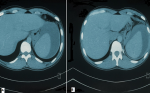

Diagnostic assessment: initial blood investigations showed anaemia with hemoglobin level of 10.5 g/dl with thick and thin blood smear positive for Plasmodium vivaxPlasmodium vivax with +2 parasitemia. The diagnosis of malaria was established and oral anti-malarial treatment (Artemether-Lumefantrine) was initiated. Within 48 hours of admission, the patient developed acute abdominal pain with abdominal guarding and hemodynamic instability. Laboratory finding showed a decrease in hemoglobin to 8.S5 g/dl. An urgent abdominopelvic computerized tomography (CT) scan showed a subcapular splenic hematoma (Figure 1) with a moderate abdominal effusion.

Figure 1: A, B) computed tomography scan of the abdomen with IV contrast showing an enlarged spleen with subcapsular splenic haematoma compressing the splenic parenchyma, consistent with spontaneous splenic rupture